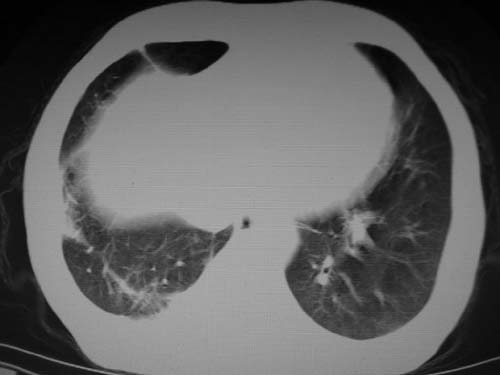

男,80岁

肺a高压征[左肺a狭窄?];肺,胸膜tb

右肺上叶结核;左肺门占位?建议增强扫描.

左下肺静脉扩张,原因?建议cta

左肺动脉异常增粗,建议增强。

1)考虑肺动脉狭窄。2)右肺上叶继发性肺结核。3)右侧胸膜增厚、钙化,左侧胸膜反应。

左肺动脉异常增粗,考虑肺动脉狭窄可能。

右肺上叶继发性肺结核。

右侧胸膜增厚、钙化,左侧胸膜反应。

左肺动脉异常增粗,建议ct增强,排除肺门肿瘤

右侧胸膜增厚、钙化,左侧胸膜反应

1)考虑左肺动脉瘤可能性大,建议增强。2)右肺上叶继发性肺结核。3)右侧胸膜增厚、钙化,左侧胸膜反应。

肺动脉段突出,左右肺门不等大,左肺门明显增大,肺动脉干及左肺动脉明显增宽,考虑先天性肺动脉狭窄瓣膜狭窄型。

)考虑肺动脉扩张,右心室增大,主动脉弓段正常位弓后段明显变小(不会是动脉导客未闭吧,不知患者有何症状病史)0。2)右肺上叶继发性肺结核。3)右侧胸膜增厚、钙化,左侧胸膜反应。

右肺上叶尖段结核;左肺下叶占位?建议增强扫描。右侧胸膜增厚;右肺局限性肺气肿。

肺动脉高压,左肺动脉瘤样扩张。